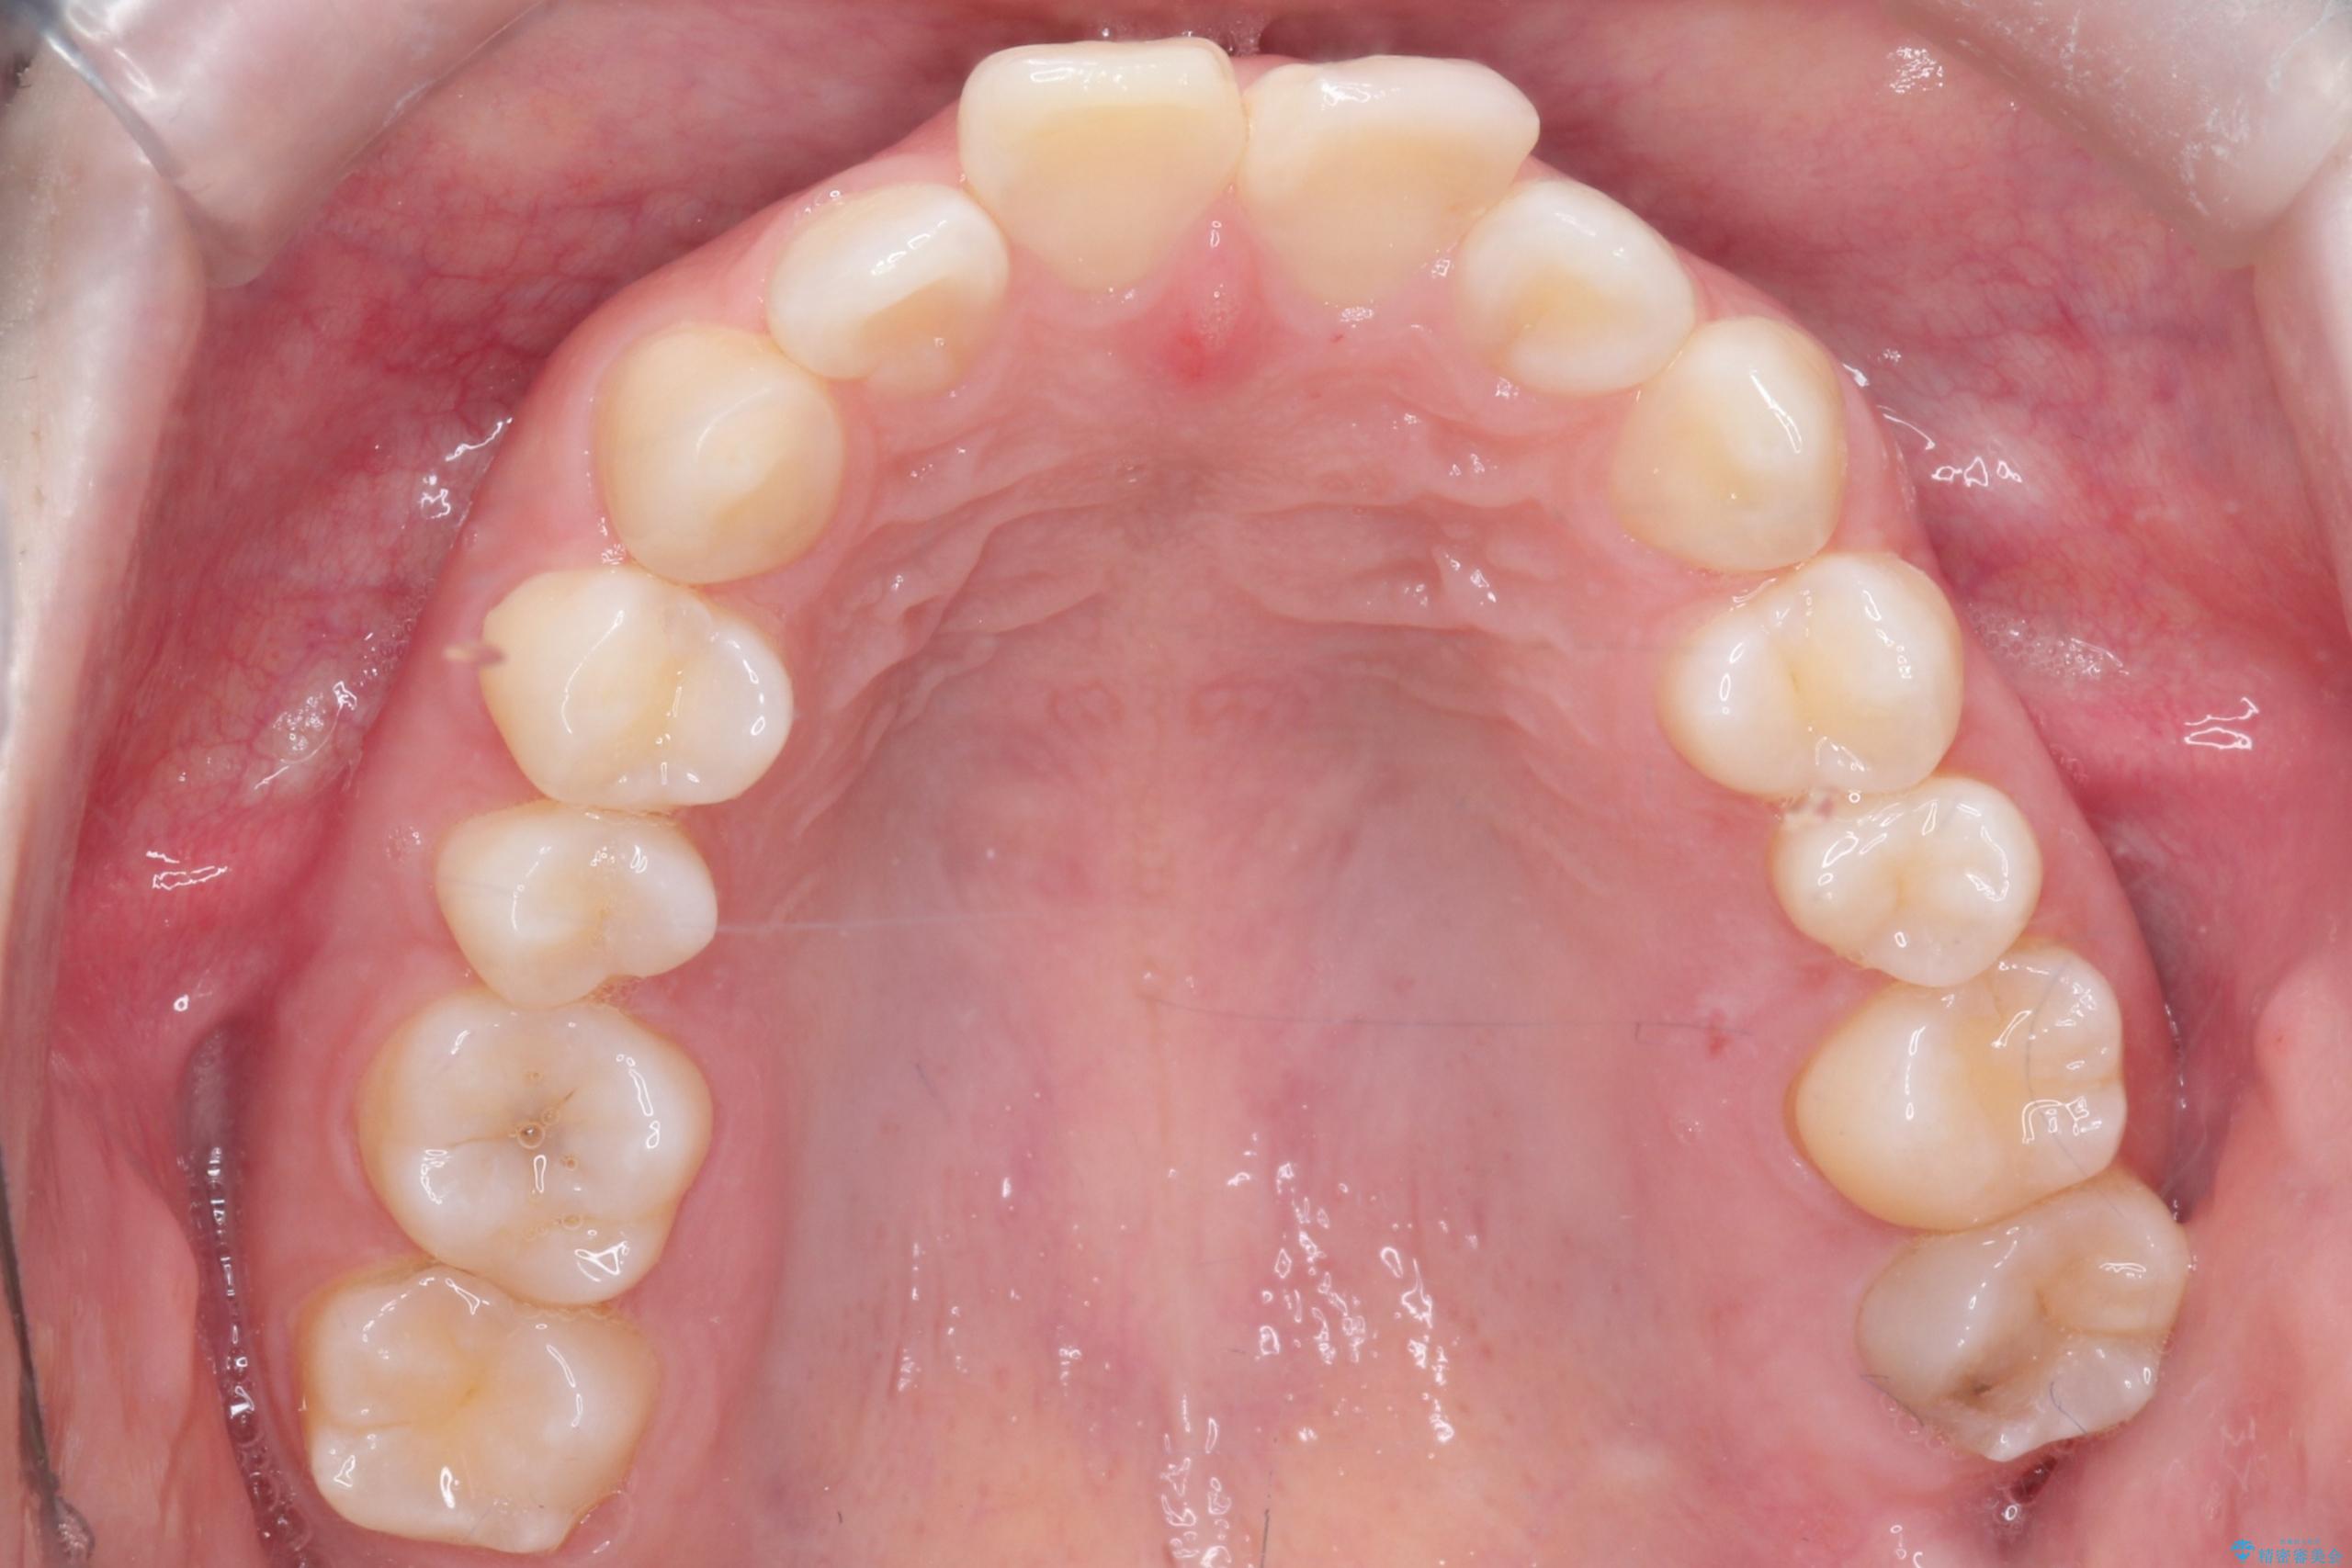

- 前歯のデコボコ(叢生)を気にされてご来院されました。精密な検査の結果、歯が並ぶスペースが不足していることが判明。患者様のご希望から、透明で目立ちにくいインビザライン(マウスピース矯正)による治療計画を立案しました。抜歯を避け、奥歯全体を奥へ動かす遠心移動という方法でスペースを確保し、前歯の叢生を解消することを目指します。

今回の矯正治療では、透明なマウスピース型の装置インビザラインを使用しました。この装置は取り外し可能で、日常生活で目立ちません。治療は、緻密に計算された計画に基づき、段階的に作製されたマウスピースを交換していくことで、奥歯から順に全体を後方へ移動させる遠心移動を実施。これにより、前歯を並べるための十分なスペースが確保され、デコボコが解消されました。抜歯することなく、機能的にも審美的にも整った美しい歯並びを獲得していただけました。